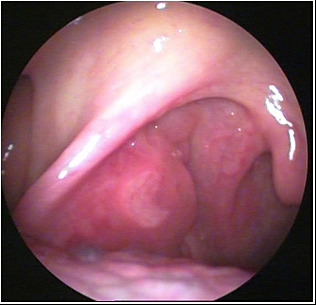

JFC Poliposis nasal bilateral.